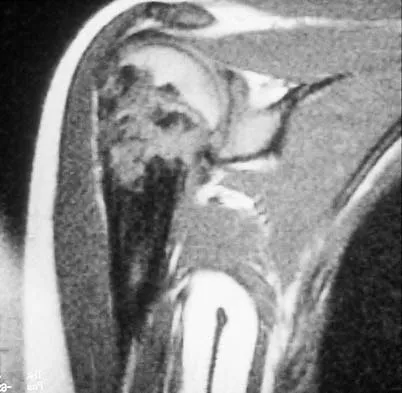

A 45-year-old man has had left thigh pain for the past 4 months. An AP radiograph, bone scan, MRI scans, and biopsy specimens are shown in Figures 6a through 6f. What is the most appropriate treatment?

Explanation

The radiograph demonstrates thickened trabeculae and thickened cortices in the left proximal femur compared to the right, and the bone scan shows increased uptake in this area. The MRI scans show thickened trabeculae with normal marrow signal. These findings are diagnostic of Paget's disease. Medical treatment, including bisphosphonates and calcitonin, is indicated for painful bone lesions. Hadjipavlou AG, Gaitanis IN, Kontakis GM: Paget's disease of the bone and its management. J Bone Joint Surg Br 2002;84:160-169.